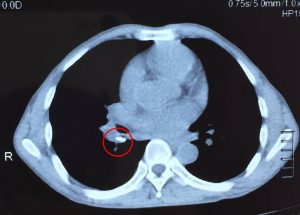

Phẫu thuật u não là một kỹ thuật khó, ngoài đòi hỏi kỹ năng của phẫu thuật viên, việc hỗ trợ của các trang thiết bị hiện đại cũng góp phần không nhỏ vào thành công của cuộc phẫu thuật. Ngày nay, với việc sử dụng hệ thống định vị trong phẫu thuật, phẫu thuật viên có thể dể dàng xác định được vị trí, kích thước u, từ đó chọn đường mổ nhỏ và gần khối u nhất, hạn chế làm tổn thương những vùng chức năng của não.

Ngày 17/01/2019, Bệnh viện Đa khoa Xuyên Á – Vĩnh Long (BVXA – VL) tiếp nhận điều trị cho bệnh nhân nam T.V.H. 53 tuổi, ngụ tỉnh Đồng Tháp vào viện với triệu chứng ho kéo dài suốt một tháng, đã được điều trị tại bệnh viện địa phương nhưng không thuyên giảm. Lần này, […]